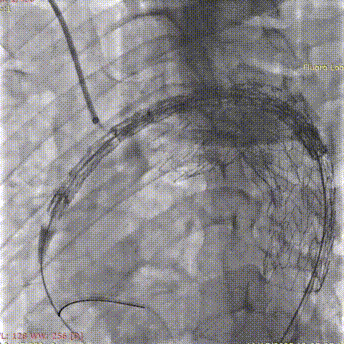

1. 患者全身麻醉后先进行弓上分支血管转流,该部分完成后,穿刺右侧股动脉及双侧肱动脉,置入金标猪尾导管进行主动脉弓部造影。

斑马导丝是治疗什么的「胸有乾坤」至简至易 行之有效—— Zone 0 TBE植入治疗弓部动脉瘤病例报道_https://www.jmylbn.com_新闻资讯_第13张

5. 右侧肱动脉长鞘造影确认支架位置。

斑马导丝是治疗什么的「胸有乾坤」至简至易 行之有效—— Zone 0 TBE植入治疗弓部动脉瘤病例报道_https://www.jmylbn.com_新闻资讯_第19张